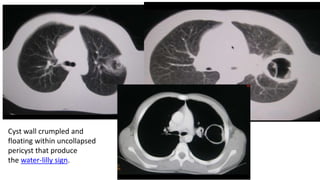

Cyst wall crumpled and

floating within uncollapsed

pericyst that produce

the water-lilly sign.